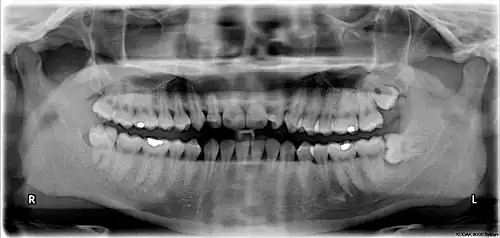

Orientation of the chart is traditionally "dentist's view", i.e. patient's right corresponds to notation chart left. The designations "left" and "right" on the chart below correspond to the patient's left and right.

ISO notation upper jaw (wisdom teeth removed) -

ISO notation lower jaw (wisdom teeth removed) -